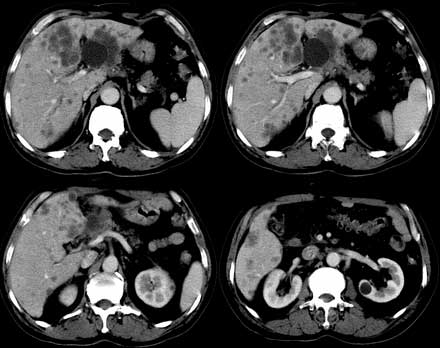

患者 男性 65岁,2005年8月行胆管癌切除术(切除胰头 胆囊及十二指肠),今行ct复查,请会诊,有没有复发?(近期患者发烧,重度黄疸)

是单纯复发还是复发伴肝内转移?我个人认为应当再考虑一下,并倾向于后者。肝总管下端内、后侧见不规则软组织块影,部分侵入肝总管内。其边缘凸凹不平且模糊不清,渐进性不均匀强化。肝总管于此处管径突然变小,其上肝总管显著扩张,内见较均匀液性密度,管壁也很光整。肝内多发低密度病灶用复发引起的肝内胆管扩张显然不能解释的通,病灶分布与胆内胆管的走行不一致。而且随着时间的延续病变更加清晰,没有强化,部分还可见牛眼征。

肯定是:胆管复发并肝内广泛转移,还有肝及胆总管周围网膜炎性改变。腹腔干后第三层面腹膜后血管间结节状影,淋巴结肿大可能,这上面没法看清!

考虑复发并转移,肝门区胆管扩张,左肾多发囊肿可能.腹腔淋巴结转移.